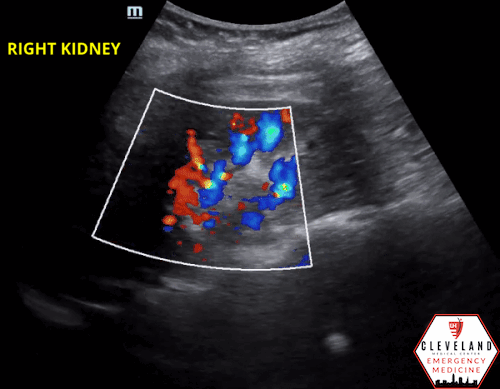

Renal POCUS was performed to evaluate for hydronephrosis and showed the following:

POCUS findings:

There is hydronephrosis of the left kidney. The right kidney is normal-appearing. Bladder views incidentally revealed a large complex, fluid-containing lesion in the pelvis (color doppler negative).

8. Apply color doppler to the kidney, particularly over the renal pelvis, to differentiate vasculature from hydronephrosis.

Hydronephrosis can commonly be confused with the medullary pyramids of the kidneys, as well as cysts or vascular prominence/malformation. Pyramids and renal cysts are distinct structures and tend to be more peripherally located compared to hydronephrosis which starts centrally. Vasculature can be differentiated from hydronephrosis with color doppler [5-7].